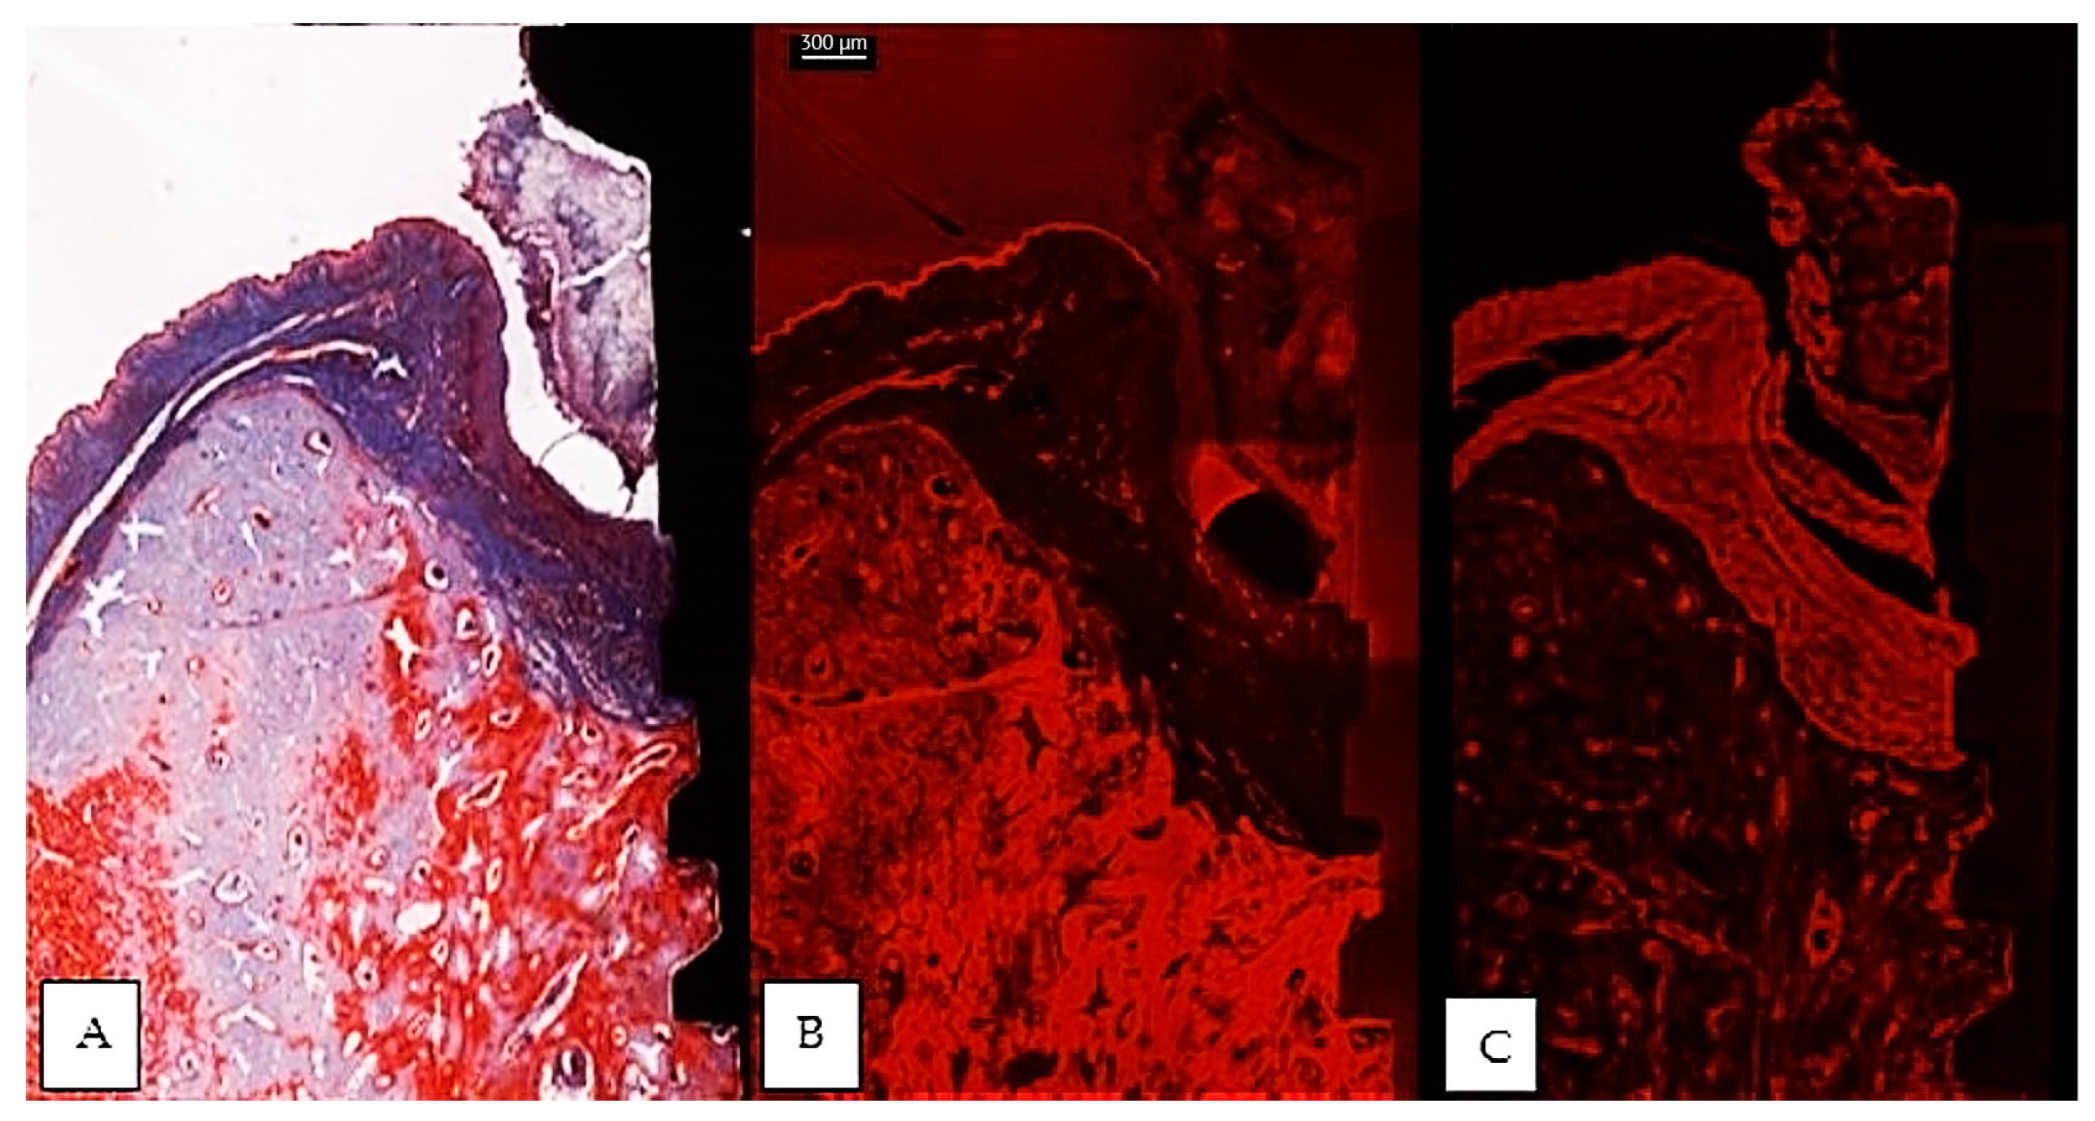

The usual light microscopy technique using pentachrome stains revealed good tissue morphology preservation; however, the opacity of the metallic implant made it difficult on some of the specimens to properly identify the implant shoulder. The CLSM thin sections were easier to scan, having a flatter surface, yet the grinding to a thin section led to minor tissue cracks in the bone component (Figure 3A,B). Furthermore, the use of mounting medium and coverslip on the thin sections induced an additional decrease in contrast, altering the quality of soft tissue morphology in the thin sections (Figure 3A,B). In both thin and thick sections, the implant shoulder was easily identifiable, except in the thick sections where the implant was lost during histological processing. The peri-implant sulcus is shallower in non-ligated specimens than in ligated ones, the bone is in contact with the implant surface and the soft tissue is in contact with the healing abutment (Figure 4). Infiltrated connective tissue (ICT) was present in contact with bone and implant (Figure 5). However, it is important to mention that the cellularity of the ICT was not visible under CLSM; therefore, LM seemed better suited for the assessment of the ICT. Epithelial lining integrity was broken, more pronounced on the oral aspect, making the identification of landmarks like aJE extremely difficult (Figure 6). This comes not as a surprise under the severe inflammation circumstances found in peri-implantitis, as this landmark is poorly identifiable even on LM. In these areas of integrity loss, the highly inflamed soft tissue was identified in direct contact with the bone and implant (Figure 7). Regarding the soft tissues, the epithelial covering is clearly identifiable on both types of evaluation (LM and CLSM).

Figure 3.

Comparative images of the same implant, between a thin section in light microscopy, Masson Goldner Anilin blue stain (A), same thin section in CLSM (B) and a thick section in CLSM (C). Morphological preservation of tissular integrity is better seen in the thick section. (implant #5, buccal aspect, bar measure for all three images is 300 µm).